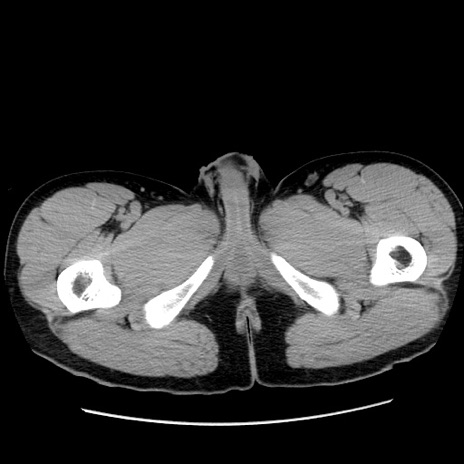

症例36(横断像)

【症例】20歳代 男性

【主訴】心窩部痛

【現病歴】今朝より上腹部痛あり。一旦軽快していたが再度出現したため救急要請。昨日夕に白身の魚を含む刺身を食べた。

【身体所見】BP 136/89mmHg、HR 74/min、BT 37.0℃、腹部:膨満、軟、心窩部に圧痛あり。反跳痛なし、筋性防御なし、腸雑音やや亢進あり。

【データ】WBC 17700、CRP 0.48